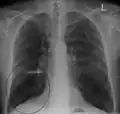

A chest X-ray is not useful to establish a diagnosis of COPD but it is of use in either excluding other conditions or including comorbidities such as pulmonary fibrosis and bronchiectasis. Characteristic signs of COPD on X-ray include hyperinflation (shown by a flattened diaphragm and an increased retrosternal air space) and lung hyperlucency.[5] A saber-sheath trachea may also be shown that is indicative of COPD.[110]

A CT scan is not routinely used except for the exclusion of bronchiectasis.[5] An analysis of arterial blood is used to determine the need for oxygen supplementation and assess for high levels of carbon dioxide in the blood; this is recommended in those with an FEV1 less than 35% predicted, those with a peripheral oxygen saturation less than 92% and those with symptoms of congestive heart failure.[111] WHO recommends that all those diagnosed with COPD be screened for alpha-1 antitrypsin deficiency.[42]